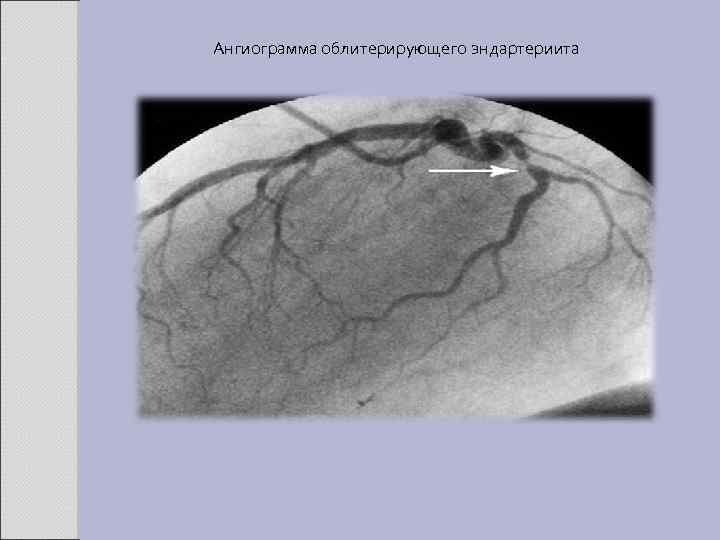

Ангиограмма облитерирующего эндартериита